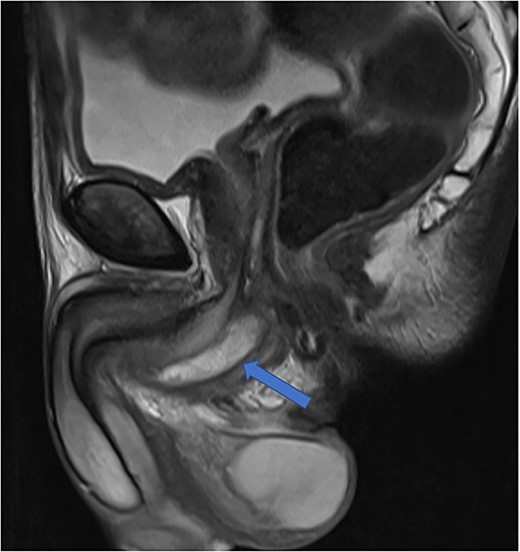

He was put on an empirical course of ciprofloxacin to treat a presumed complicated UTI, and a pelvic MRI was requested. Urine culture grew an Enterobacter cloacae organism. The MRI scan revealed a 7 × 3 cm perineal collection inferior to the prostate and adjacent to the membranous urethra, with increased wall enhancement and fluid with restricted diffusion, with a diagnosis of Cowper’s syringocele (Fig. 3).

Case 2: T2-weighted sagittal MRI image demonstrating a complex, cystic perineal collection (blue arrow), seen in relation to one of the corpus cavernosa (yellow arrow).